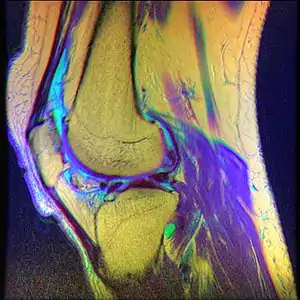

| Diagnostic method | MRI |

While the term chondromalacia sometimes refers to abnormal-appearing cartilage anywhere in the body,[9] it most commonly denotes irritation of the underside of the kneecap (or "patella"). The patella's posterior surface is covered with a layer of smooth cartilage, which the base of the femur normally glides smoothly against when the knee is bent. However, in some individuals the kneecap tends to rub against one side of the knee joint, irritating the cartilage and causing knee pain.[10]